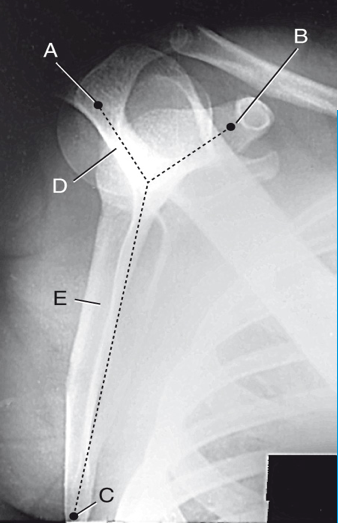

clavicle

A

coracoid process

B

glenoid fossa

C

acromion process

D

lesser tubercle

E

humeral head

F

external rotation

position of humerus?

internal rotation

neutral rotation